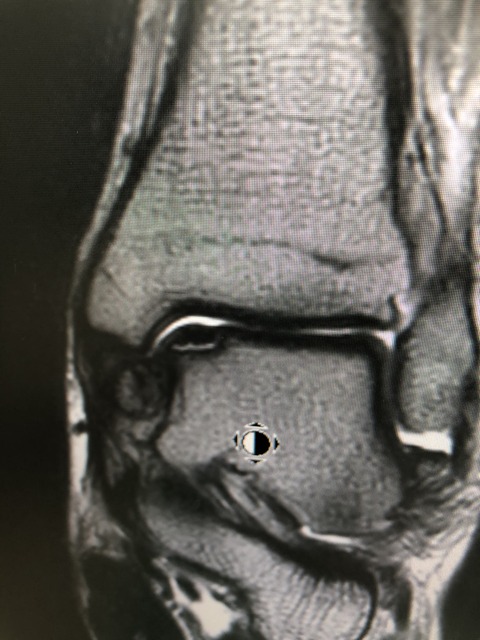

デッドボール受けた瞬間に膝を強く捻り受傷

MRIで前十字靭帯の部分断裂、半月板の損傷が

ありますが、3週間で、現在のところを幸い、

全く痛みなく、普通にジョギング等

できるなりました

トレーナー、監督、本人と相談の上、

今シーズンは、復帰させます